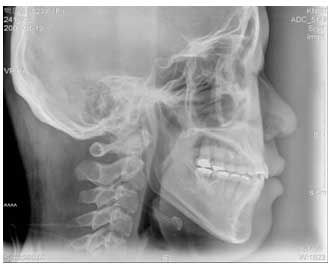

Puntos cefalometricos

Ubicación de puntos cefalometricos